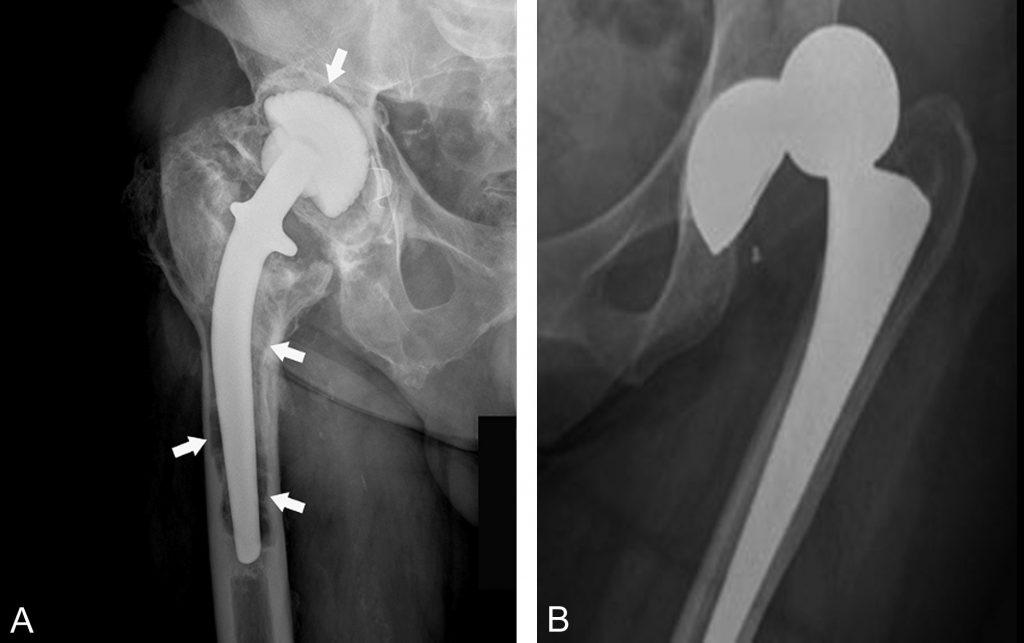

Fig. 82.1 Complication des prothèses.

(A) Descellement de la tige fémorale et de la pièce acétabulaire d’une prothèse totale de hanche : radiographie de la hanche droite de face montrant des liserés clairs aux interfaces os/prothèse (flèches). (B) Luxation d’une prothèse totale de hanche gauche.

Source : CERF, CNEBMN, 2022.

- d’une luxation : perte des rapports normaux entre les surfaces articulaires ;

- d’un descellement non septique : liséré clair périprothétique de 2 mm et plus, régulier, ou déplacement manifeste des pièces prothétiques (cf. figure 82.1) ;

- d’un descellement septique : ostéolyse périprothétique avec un liseré périprothétique irrégulier, des appositions périostées, un épanchement articulaire ou des collections péri-articulaires.